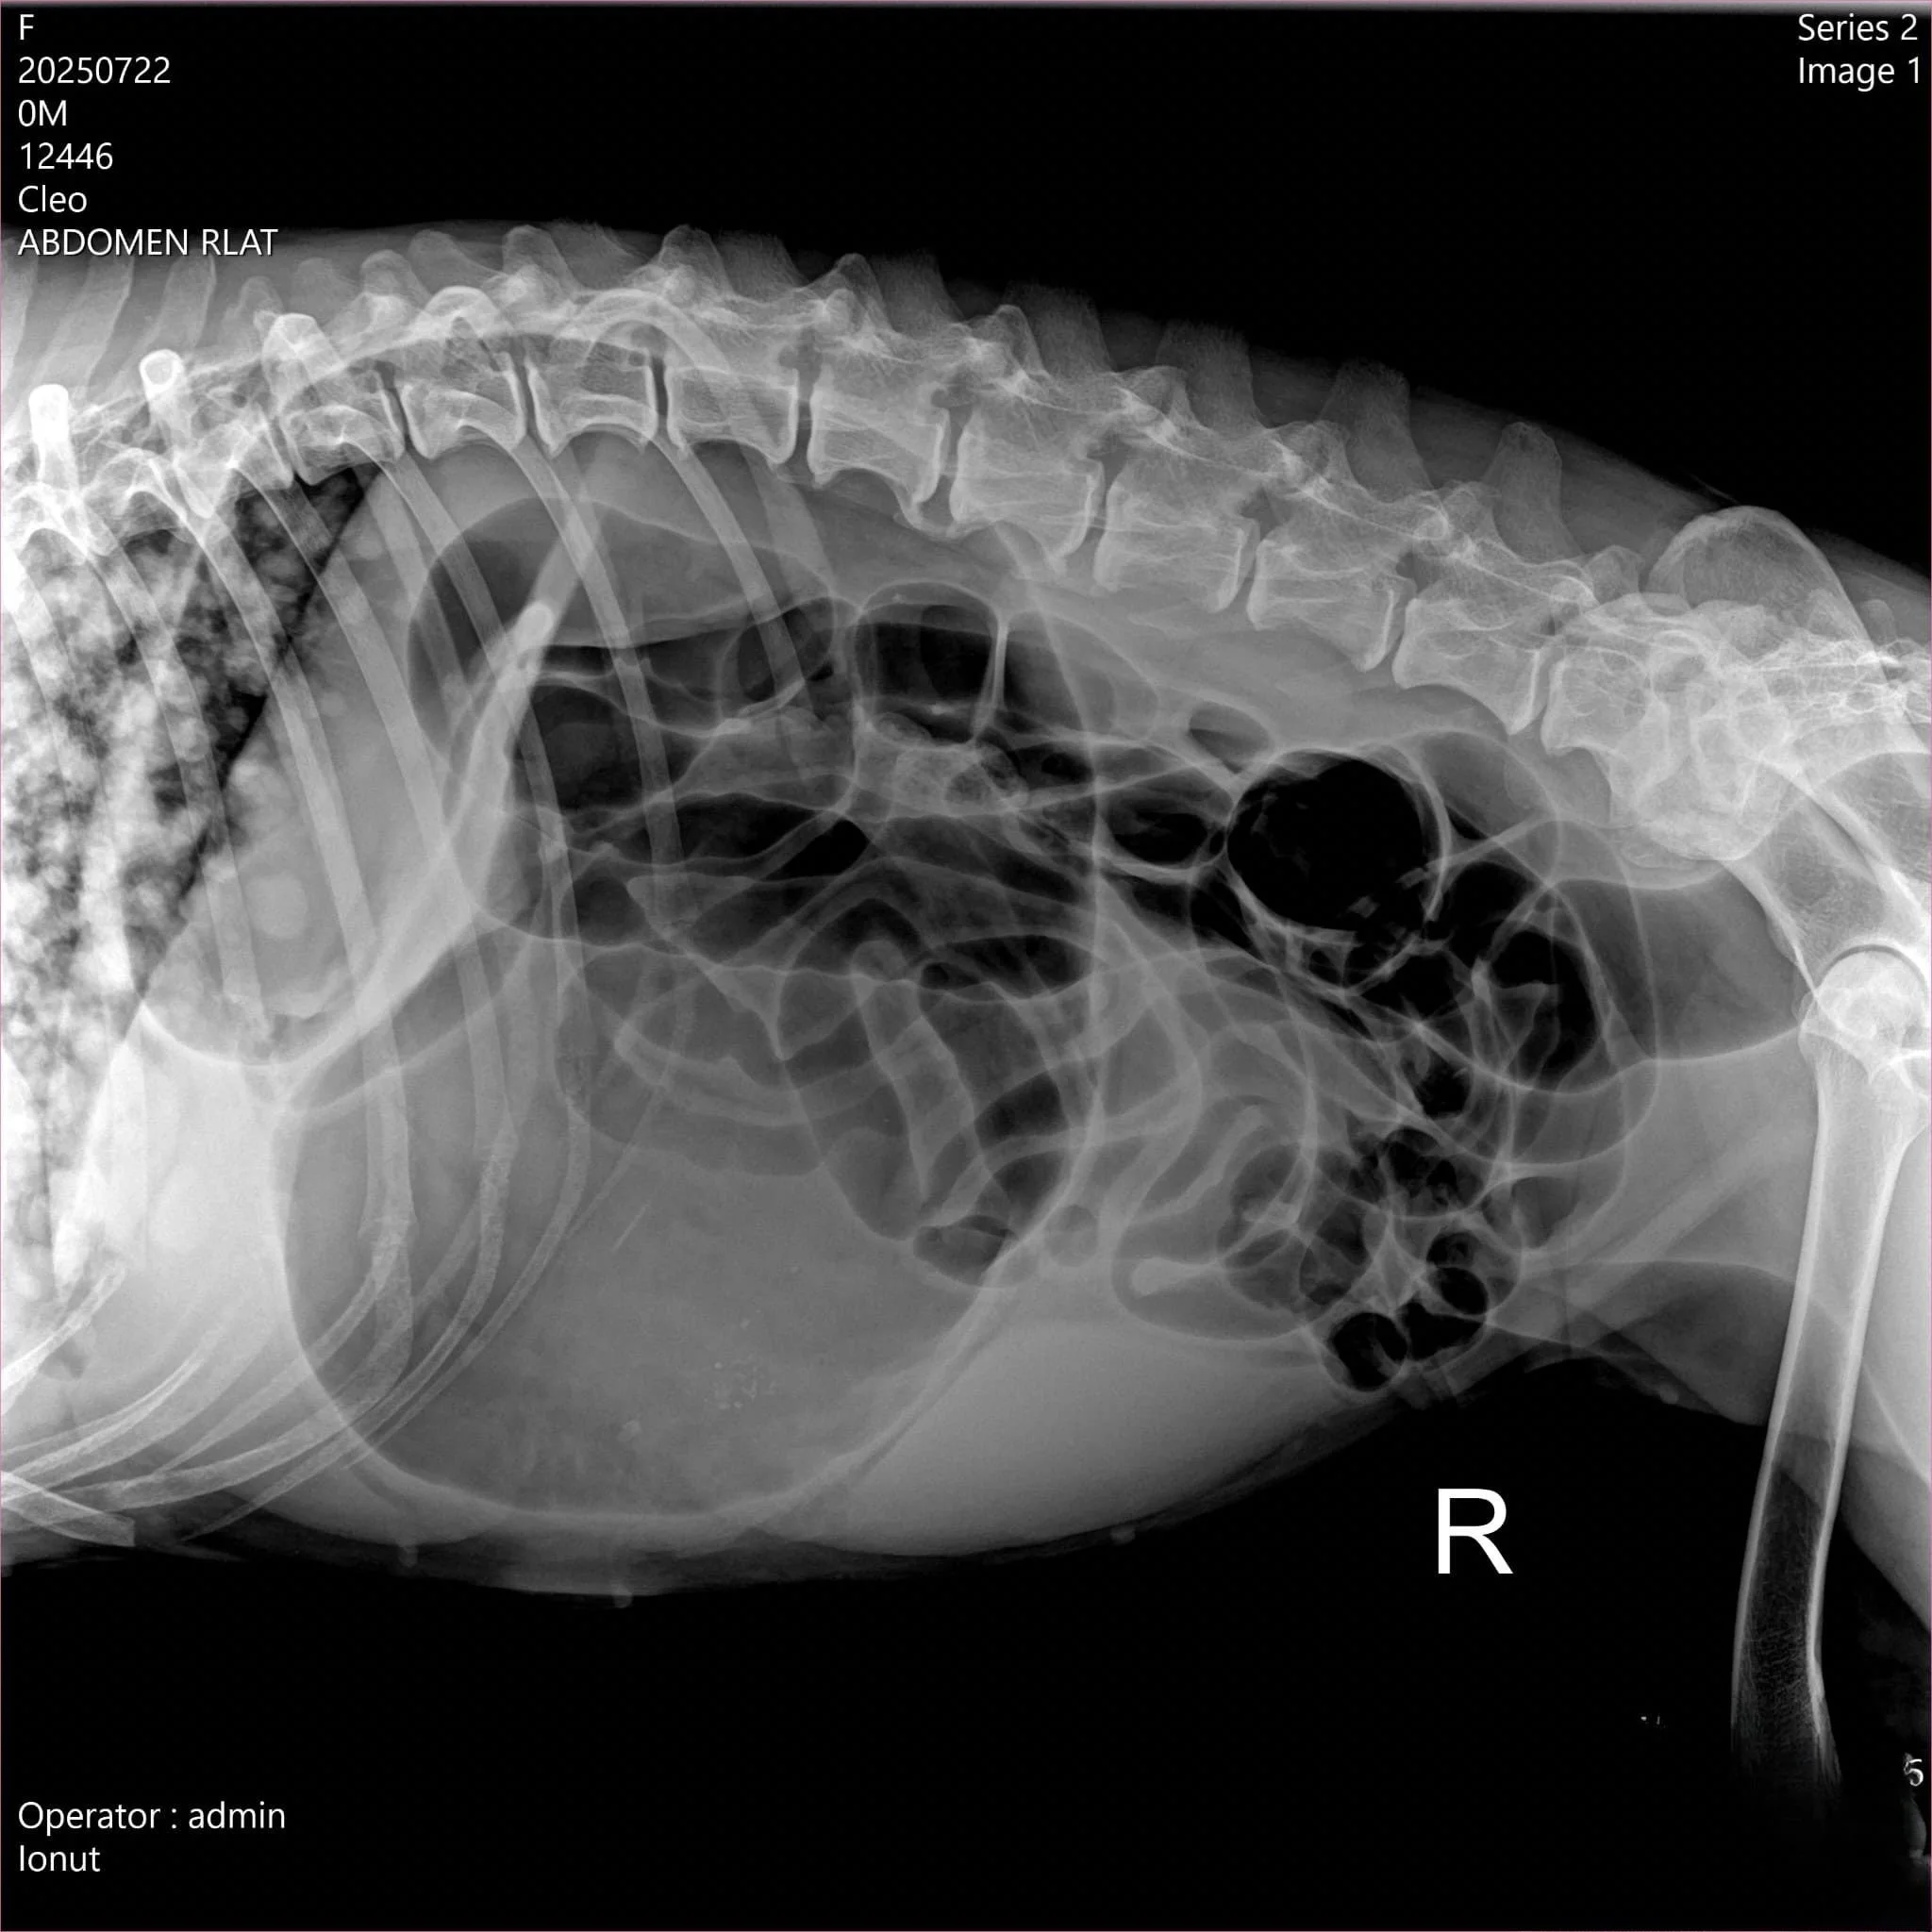

La sosirea în clinică, medicul veterinar va efectua un examen fizic complet, acordând atenție parametrilor hemodinamici: puls, tensiune arterială și perfuzie capilară. Radiografia abdominală este examenul de elecție pentru confirmare: se observă o imagine cu aspect de “manușă de box” a stomacului. În paralel, se recoltează probe de sânge pentru evaluarea parametrilor sanguini, a electroliților și a parametrilor biochimici (funcție hepatică, renală). Un ECG poate evidenția aritmii secundare hipoperfuziei.